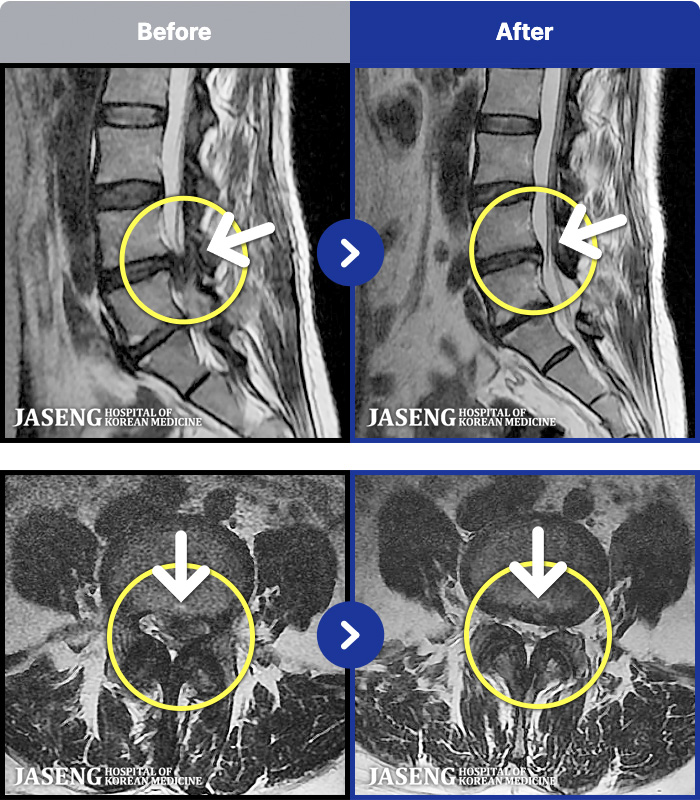

MRI ũ ʸ Ȯϼ.

ȯںп Ǹ ǿ ԿǾ, ο ġ ۿ Ƿ ġḦ Ͻñ ٶϴ.